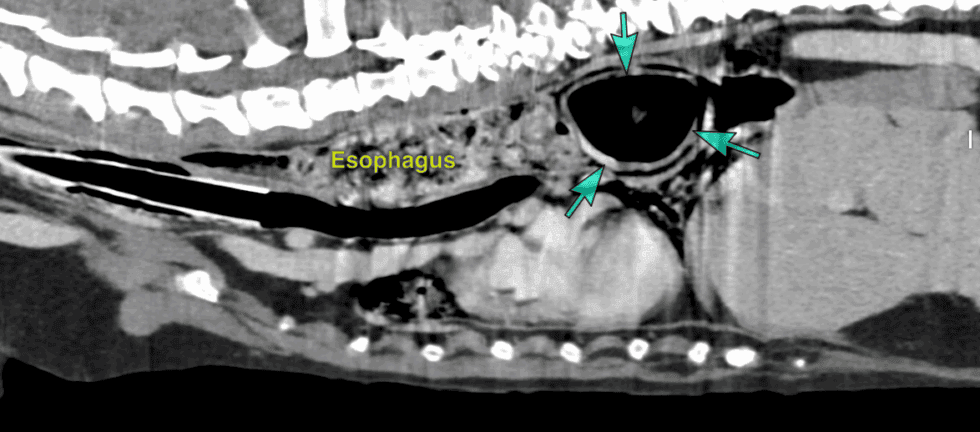

The Diagnostic Imaging team performed a CT scan to determine the cause of Ernie’s symptoms, and upon examination a foreign body, identified as a tennis ball, was discovered in Ernie’s food pipe (oesophagus). The ball appeared intact, albeit squashed, and firmly lodged in Ernie’s throat.

Due to the size of the ball and how much of the passageway was blocked, removal would be difficult. The original plan was to push the ball into the stomach and remove it with surgery. However, after several attempts, the ball couldn’t be moved downwards. Taking a different approach, a stomach tube was carefully passed beyond the ball and used to pull the ball upwards towards the mouth. Forceps were then used to remove the ball.